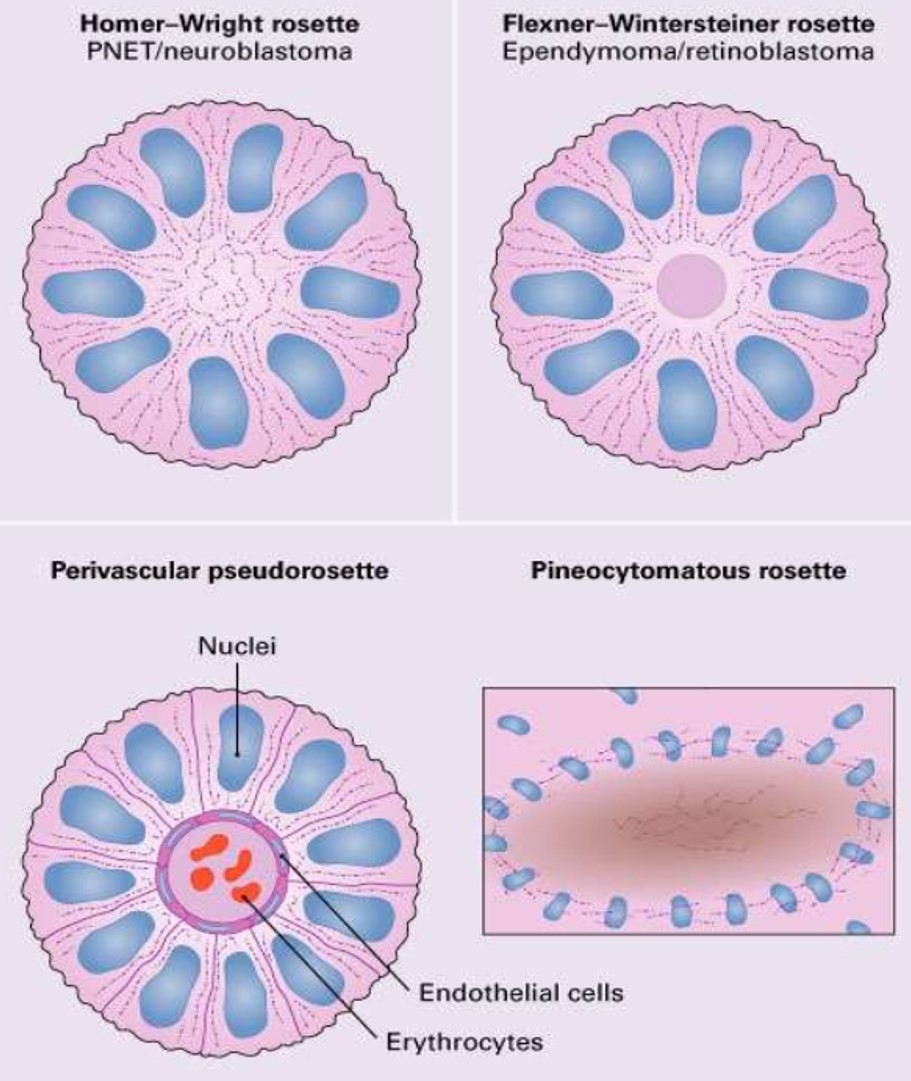

- Homer-Wright rosette